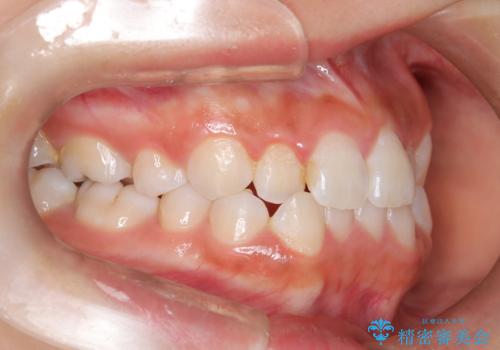

- 子供のころに矯正治療をされていたが、後戻りをしてしまったという20代女性の患者様です。上顎左右の2番が、咬合時に下顎の歯よりも内側に入っているクロスバイトという状態でした。奥歯の咬合関係は変えずに、マウスピース矯正にて前歯の並びを綺麗なアーチに仕上げました。再度後戻りしてしまうリスクを軽減させるために、リテーナー(保定装置)をお渡ししています。